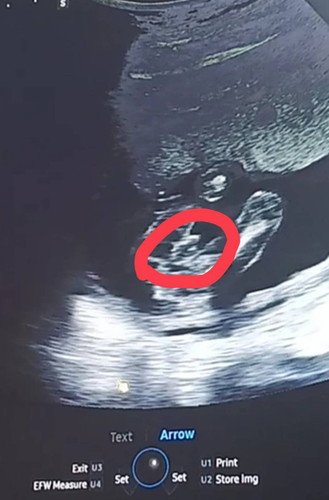

ซาวอายุครรภ์ 16 วีคค้ะ ลูกคนที่สอง คุณหมอบอกว่า จู๋โผล่ค้า 😂